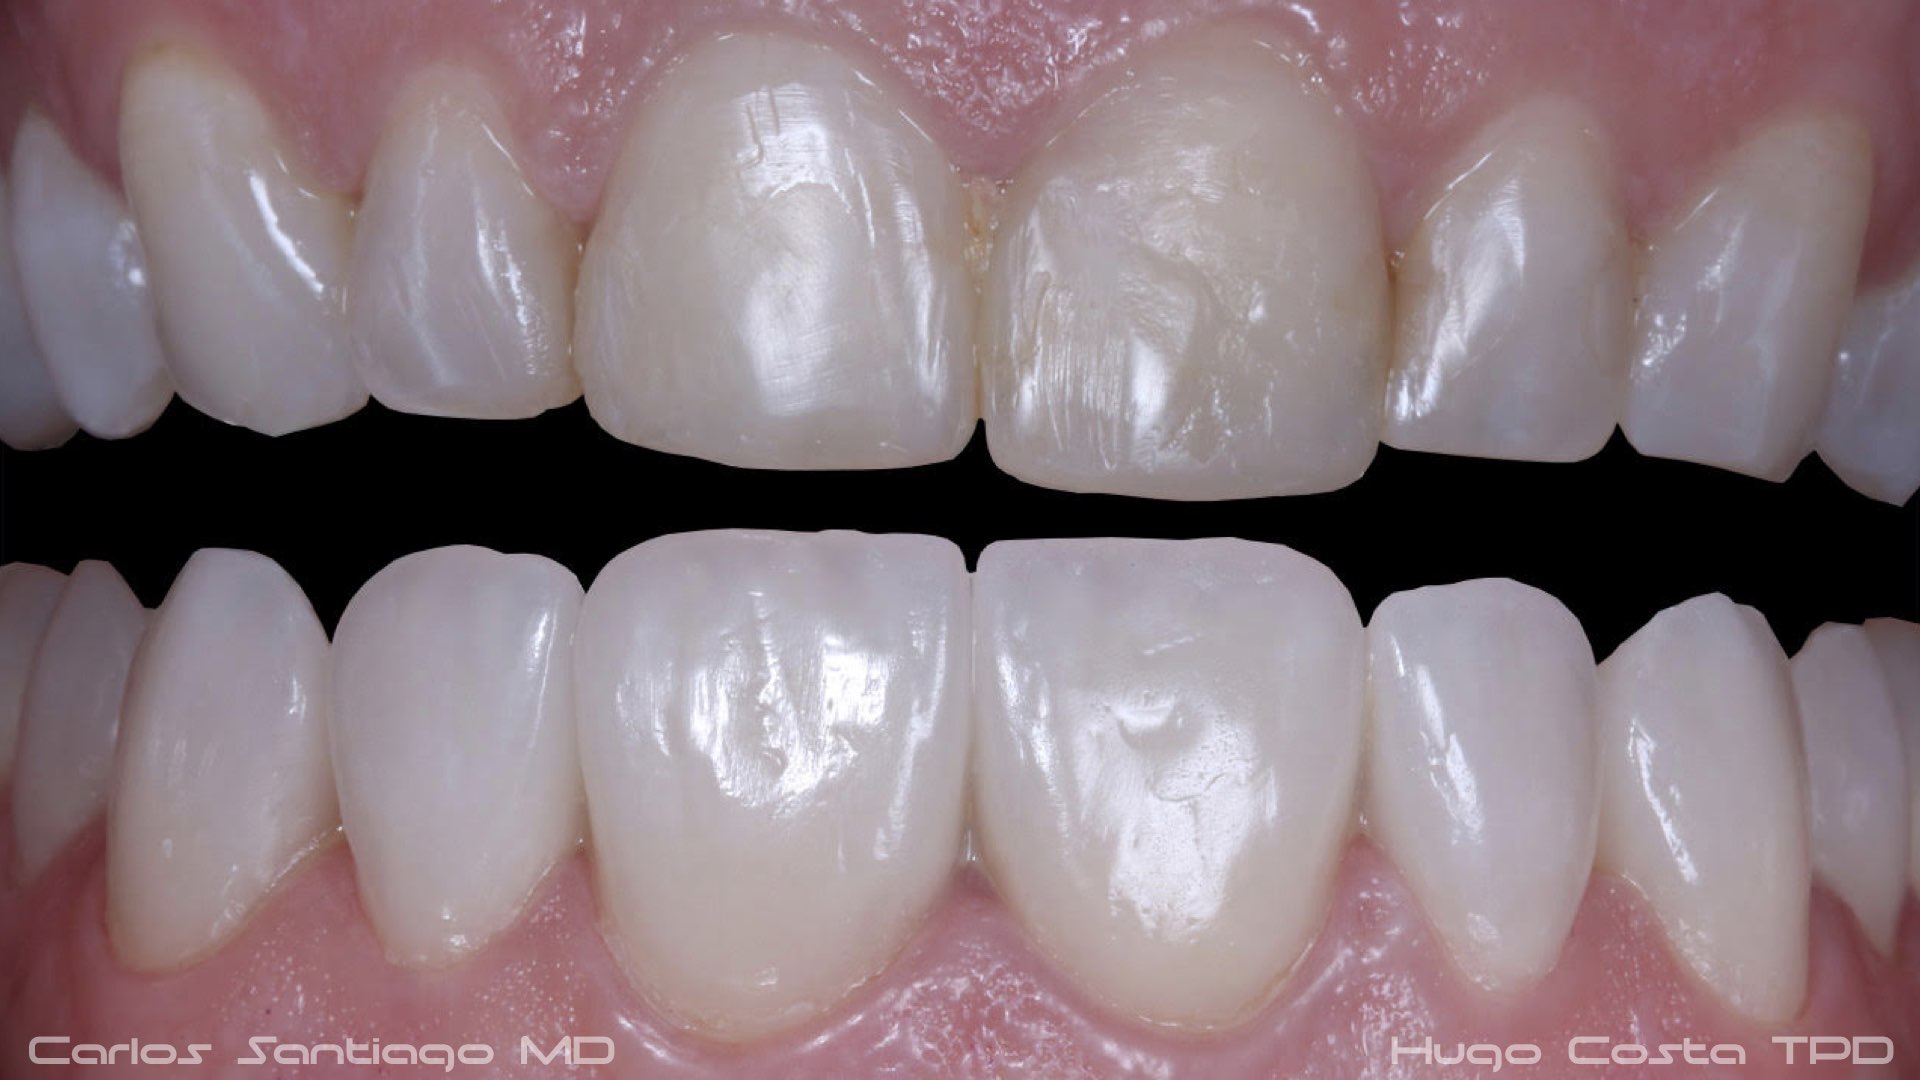

As Facetas Cerâmicas (lentes de contacto dentárias ou laminados), permitem corrigir da maneira mais estética e conservadora possível, problemas de forma e tamanho, côr e posição dos dentes, bem como substituir restaurações antigas e inestéticas.

São aderidas químicamente ao esmalte dentário de uma forma permanente, com o objectivo de melhorar a estética dos nossos pacientes.